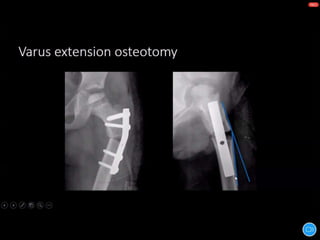

Reconstructive procedures

Valgus extension osteotomy

indication -hinge abduction of hip

TREATMENT Reconstructive procedures Valgus extensionosteotomy indication -hinge abduction of hip Cheilectomy indication – malformed femoral head with lateral protuberance Coxa plana Chiari osteotomy indication – malformed femoral head with lateral subluxation Trochanteric advancement indication – premature capital femoral physeal arrest Greater trochanteric epiphysiodesis indication – premature capital femoral physeal arrest Shelf augmentation procedure indication – coxa magna coxa magna & lack of acetabular coverage